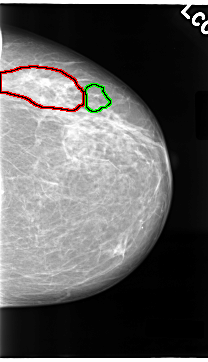

C_0087_1.LEFT_CC

FILE: C_0087_1.LEFT_CC.OVERLAY

TOTAL_ABNORMALITIES 2

ABNORMALITY 1

LESION_TYPE CALCIFICATION TYPE PLEOMORPHIC DISTRIBUTION CLUSTERED

ASSESSMENT 5

SUBTLETY 5

PATHOLOGY MALIGNANT

TOTAL_OUTLINES 1

BOUNDARY

ABNORMALITY 2